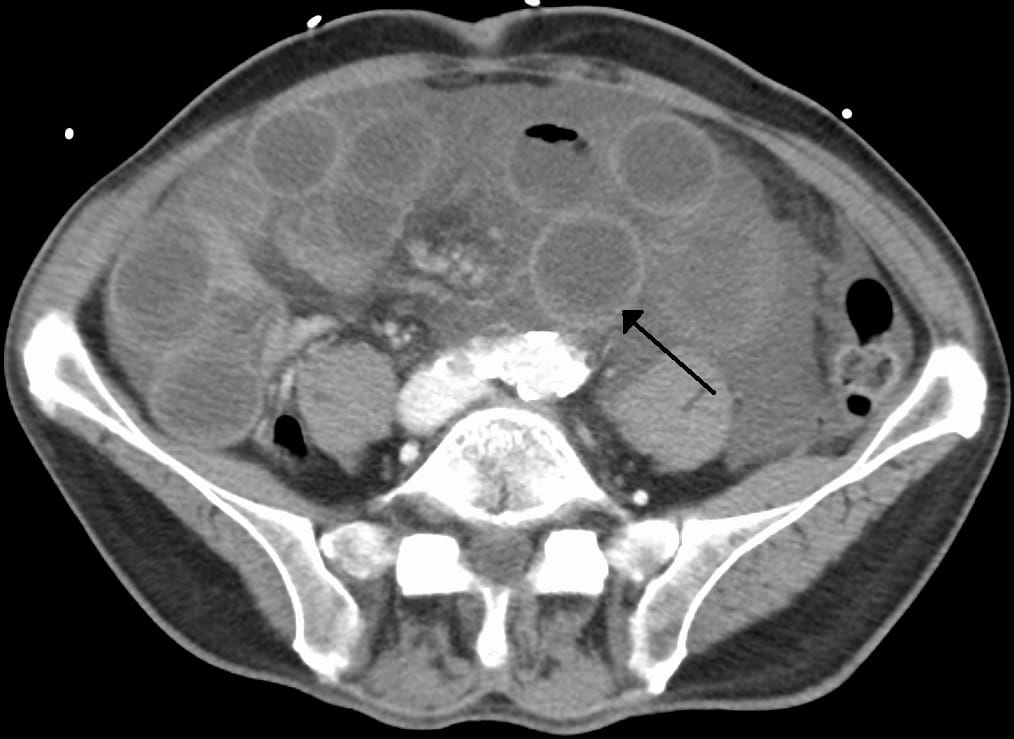

Fourth stage of small bowel ischemia with infarction. A Digital

Fourth stage of small bowel ischemia with infarction. A Digital Causes Bowel Infarction Bowel ischemia can affect a small or large intestine and can occur by any cause, which leads to intestinal blood flow reduction. Sudden loss of blood flow to the small intestine is called acute mesenteric ischemia. This is an uncommon medical condition,. Colonic ischaemia, also called ischaemic colitis, affects your large intestine (large bowel). Hardening and narrowing of the arteries,. Causes Bowel Infarction.

Small bowel infarction Image Causes Bowel Infarction Hardening and narrowing of the arteries, or a clot (thrombosis) blocking an artery, are the. The acute type is often caused by a. Sudden loss of blood flow to the small intestine is called acute mesenteric ischemia. Intestinal ischemia, which can affect the small or large intestine, can be caused by any process that reduces intestinal blood. This is an. Causes Bowel Infarction.